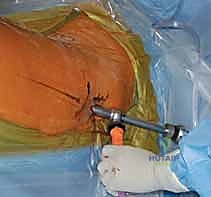

3. إحداث الشق الجراحي ونقطة الدخول

من خلال شق جراحي صغير جداً (حوالي 3 إلى 5 سم) أعلى الفخذ (فوق المدور الكبير)، يتم الوصول إلى قمة عظمة الفخذ. يتم إدخال سلك دليلي (Guide Wire) دقيق لتحديد نقطة الدخول المثالية للقناة النخاعية.

6. التثبيت السفلي (Distal Locking)

لضمان عدم دوران العظمة حول المسمار، يتم إدخال مسمار أو مسمارين صغيرين في الجزء السفلي من المسمار النخاعي عبر شقوق جلدية دقيقة جداً (لا تتجاوز 1 سم).

7. الإغلاق والتعافي

تُغلق الشقوق الجراحية الصغيرة بغرز تجميلية، وتُغطى بضمادات معقمة. يُنقل المريض إلى غرفة الإفاقة للمراقبة قبل العودة إلى غرفته. العملية بأكملها تستغرق عادة من ساعة إلى ساعتين بفضل خبرة وكفاءة الدكتور هطيف.